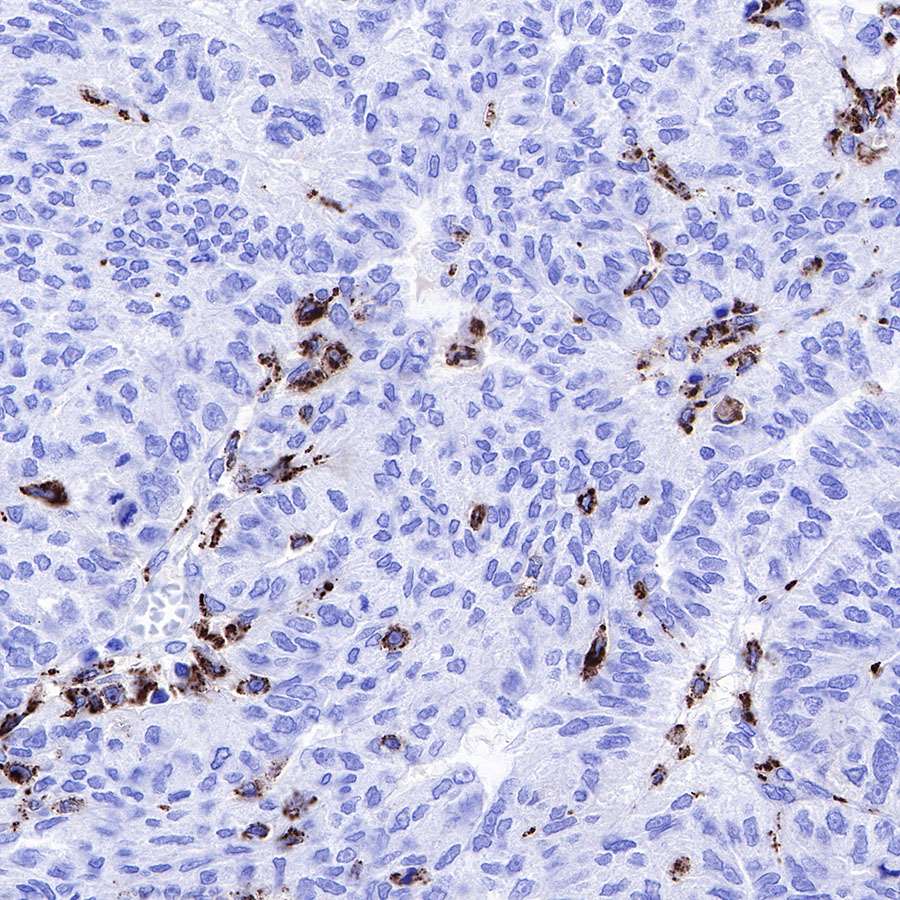

IHC shows positive staining in paraffin-embedded human ovarian carcinoma. Anti-CD68 antibody was used at 1/1000 dilution, followed by a HRP Polymer for Mouse & Rabbit IgG (ready to use). Counterstained with hematoxylin. Heat mediated antigen retrieval with Tris/EDTA buffer pH9.0 was performed before commencing with IHC staining protocol.